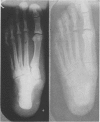

Read in part before the John A. Andrew Clinical Society, Tuskegee Institute, Alabama, April 1946.

This Article has been released for publication by the Division of Public Relations of the War Department. I am indebted to Sgts. Romey Keyes, Calvin Cleveland, and Irie Leonard for their x-ray technical assistance.